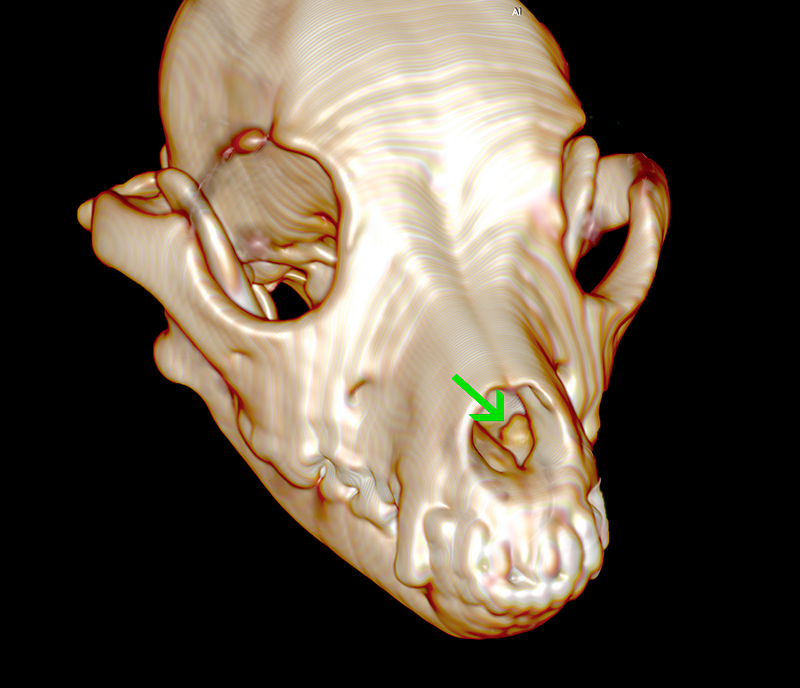

Renderización 3D del mismo animal de la tomografía lateral que nos proporciona una idea del volumen a vaporizar durante la cirugía. La osificación parcial del tumor que muestra la tomografía, hará necesario el trabajo en modo contacto que maximice la densidad de poder del haz láser